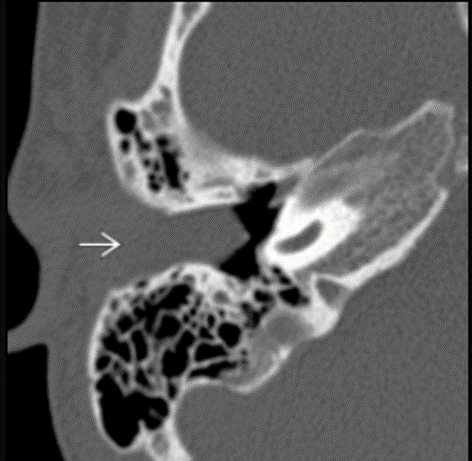

Accessory ossicle

Axial bone CT shows an ovoid bone with cortex and marrow space in the location of the posterior portion of the cartilaginous EAC. No stalk of attachment is visible. Accessory ossicles are rare in this area.